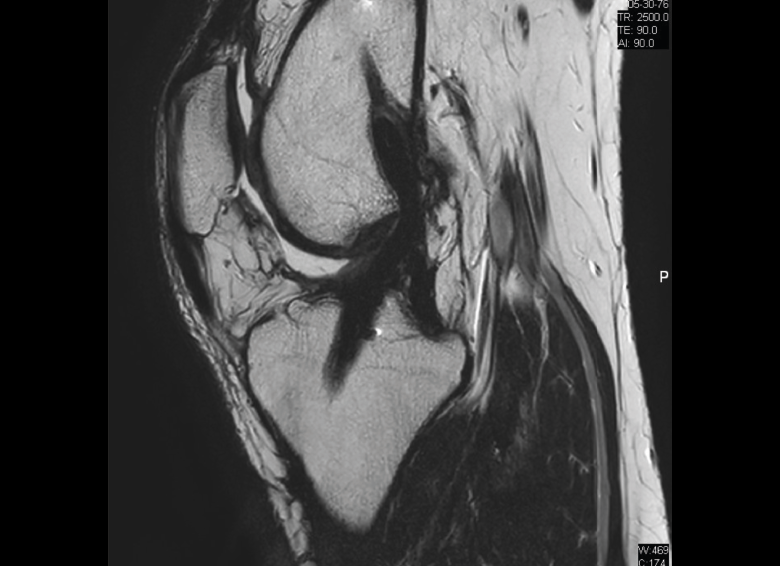

4.3. Osteocondritis

En la osteocondritis se aprecia una lesión subcondral caracterizada por resorción ósea, colapso y la formación de un secuestro.

El estudio por RM es una herramienta valiosa para diagnosticar e identificar las lesiones del cartílago. Conocer el aspecto del cartílago y saber cuánto y cuándo se lesiona, basándose en las clasificaciones actuales, permiten al radiólogo proporcionar la máxima información al clínico(20).

Figura 53. Corte de secuencia sagital (A) y axial (B) T2 Fat-Sat de RM de rodilla: lesiones osteocondrales en el fémur y la rótula.

Numerosos estudios demuestran la utilidad de la RM para definir la estabilidad o inestabilidad de la lesión en la osteocondritis, destacando su carácter no invasivo y la capacidad de valorar la progresión y la respuesta al tratamiento(21)(Figuras 53 y 54).

Figura 54. Corte de secuencia T1 y T2 Fat-Sat coronal de resonancia magnética: gran osteocondritis en el cóndilo femoral interno con edema en la medular adyacente.